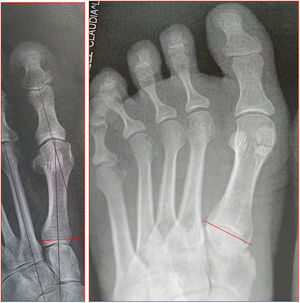

Angulo de valgo interfalángico entre los ejes longitudinales de falange proximal y el primer metatarsiano, normal hasta 10. Este ángulo elevado empeora clínicamente la deformidad y requiere osteotomía de la falange (fig. 8).

Angulo intermetatarsianoEs el ángulo entre los ejes longitudinales de primer y segundo metatarsiano, normalmente es menor de 12 grados, cuando esta aumentado se llama metatarso primo varo o aducto y deberá corregirse con osteotomía (fig. 9).